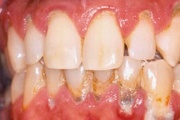

Krooniline parodontiit

Krooniline parodontiit on mikroobide poolt põhjustatud hammaste tugikudede põletik, mille tulemusena tekib progresseeruv alveolaarluu (nähtav röntgenograamil) ja periodontaalligamendi destruktsioon, igemetaskute moodustumine, igeme retsessioon või mõlemad kahjustused kombineeritult. Loe edasi »

- igemed veritsevad (19)

- igemed punetavad (21)

- ige on paistes (mädapunn)

- igemed on tursunud/vohavad (17)